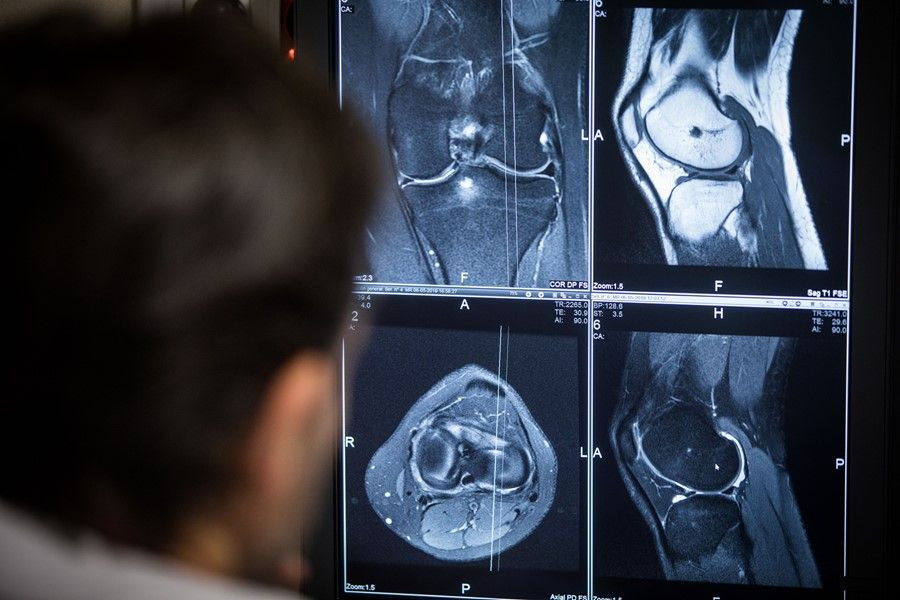

En este nuevo estudio, los investigadores trataron de investigar el efecto de los niveles de vitamina D en los resultados de la función y los factores de riesgo de dolor moderado a severo en las mujeres posmenopáusicas después del reemplazo total de rodilla. Este procedimiento se recomienda con frecuencia para tratar la artrosis de rodilla avanzada cuando el tratamiento no quirúrgico ya no es eficaz. Aunque el procedimiento es seguro, muchas mujeres experimentan dolor postoperatorio.